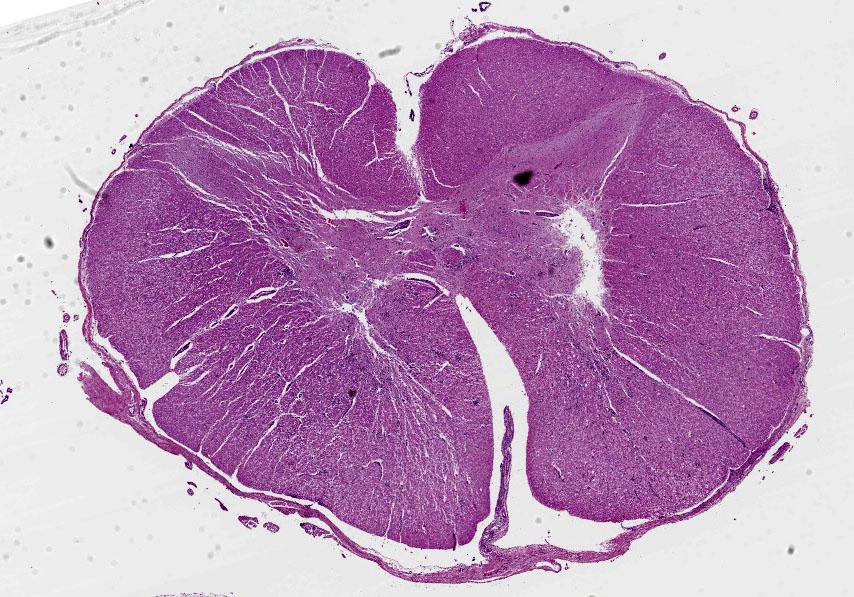

Brain, cerebellum and brainstem: In the brainstem gray matter, there are random multifocal, mild to moderate, variably discrete, infiltrates of hypersegmented and fragmented neutrophils, admixed with fewer mononuclear cells, consistent with microabscesses. Brainstem neurons within and adjacent to the neutrophilic infiltrates are pale, with central chromatolysis, consistent with neuronal degeneration. There are scattered microglial cells, mild gray matter spongiosis and infrequent microhemorrhages. Scattered blood vessels are lined by plump endothelial cells and have perivascular mild infiltrates of predominantly lymphocytes, with fewer neutrophils (perivascular cuffs). The cerebellar leptomeninges are multifocally, mildly infiltrated by predominantly lymphocytes, with fewer admixed neutrophils.

Cervical spinal cord: In the gray matter and white matter, there are scattered, variably discrete, random multifocal, mild to moderate, infiltrates of neutrophils and mononuclear cells, consistent with microabscesses. There is neuronal degeneration, spongiosis, microgliosis, and swollen axons. Blood vessels are lined by plump endothelial cells and have perivascular mild to moderate infiltrates of predominantly lymphocytes, with fewer admixed neutrophils and infrequent plasma cells. The leptomeninges are multifocally expanded by mild to moderate infiltrates of lymphocytes with infrequent admixed neutrophils.

1. Brain, cerebellum and brainstem: Meningoencephalitis, lymphocytic, multifocal, mild to moderate, with multiple brainstem neutrophilic microabscesses.

2. Cervical spinal cord: Meningomyelitis, lymphocytic, multifocal, moderate, with multiple neutrophilic microabscesses.

There are few or no gross lesions in listeric encephalitis. Leptomeningeal opacity and cloudy cerebrospinal fluid may be the only findings seen at necropsy. Typically, microscopic lesions of listeric encephalitis are limited to the brainstem and cervical spinal cord. They include microabscesses, glial nodules, perivascular accumulation of lymphocytes and lymphocytic leptomeningitis. Gram-positive bacilli can be found within the microabscesses.

1. Cervical spinal cord: Meningomyelitis, suppurative, subacute, multifocal, moderate, with microabscesses.

2. Brainstem and cerebellar white matter: Leukoencephalitis, suppurative, subacute, multifocal, mild to moderate, with microabscesses and lymphohistiocytic meningitis.